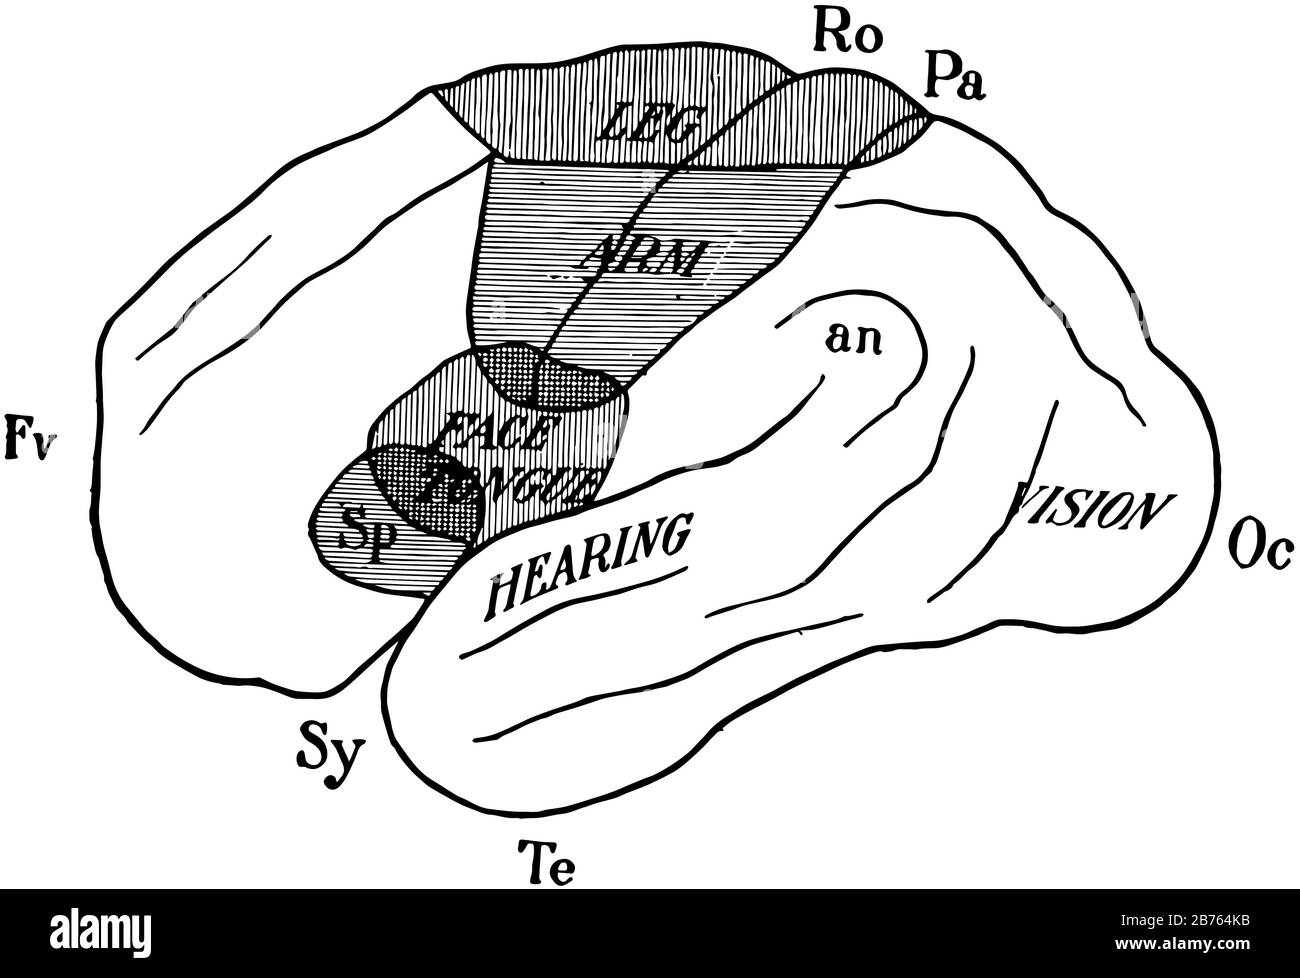

RF2B764KB–Diagramma della superficie esterna dell'emisfero cerebrale sinistro per illustrare la localizzazione delle funzioni, il disegno a linee d'annata o l'illustrazione dell'incisione.